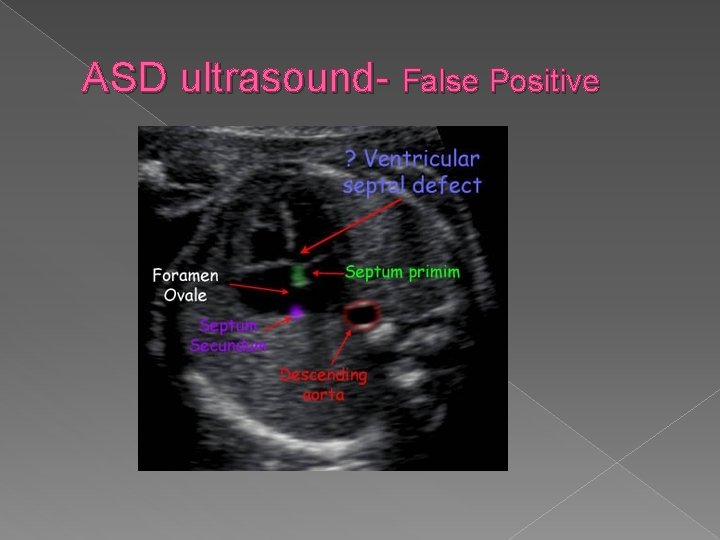

Structural Cardiac Anomalies Atrial Septal Defect (ASD) � Any abnormal opening between the atria is referred to as an atrial septal defect. ASDs are associated with a variety of cardiac and chromosomal abnormalities. Diagnosis is difficult because of the normal patent foramen ovale. Sonographic findings: � Relies on demonstration of echo dropout at the level of atrial septum � Since foramen ovale is normally open, prenatal diagnosis is unlikely.

ASD- Atrial septal defect Any abnormal opening between the atria is an ASD. Hard to diagnosis because of the normal patent foramen ovale.

ASD ultrasound- False Positive